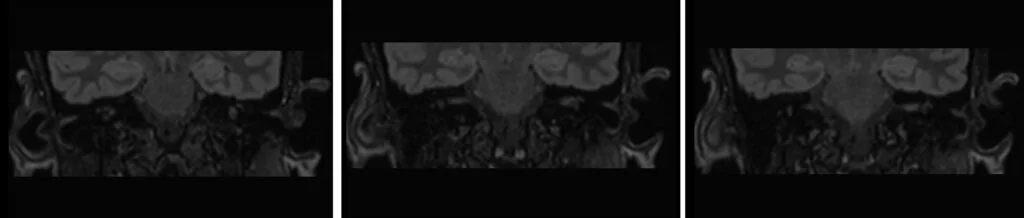

T2 SPACE FLAIR 3D axial .8mm images

T2 SPACE FLAIR 3D coronal reconstructed images